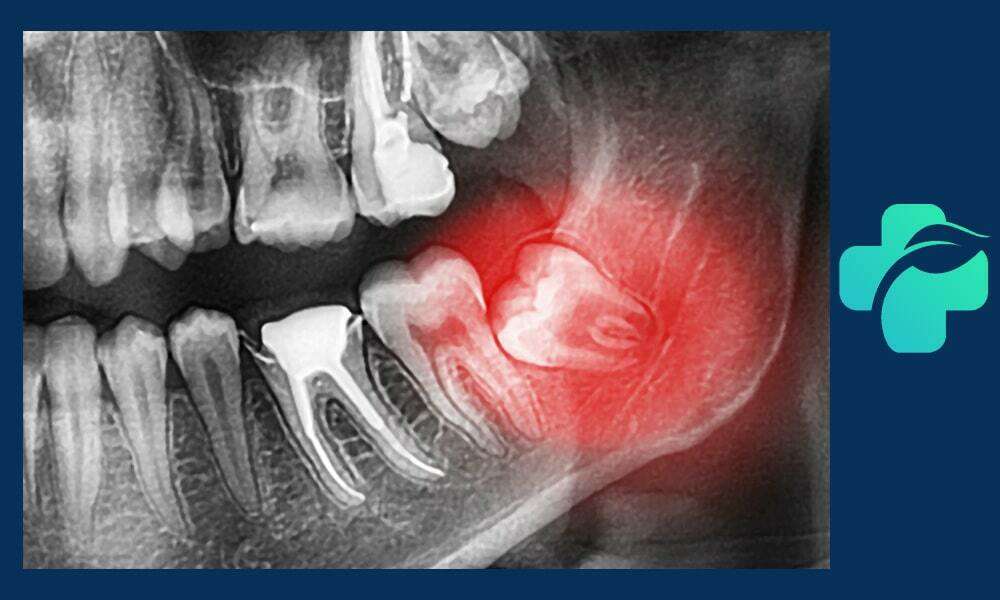

معمولاً پزشک با بررسی عکس پرتوی ایکس، بهترین روش درمان جراحی دندان عقل نهفته را انتخاب می کند.

گاهی این دندان ها به دلیل نداشتن فضای کافی یا رشد نادرست، دندان عقل نهفته می شوند؛ یعنی به طور کامل یا جزئی از لثه بیرون نزده اند. این وضعیت باعث درد، عفونت، التهاب و حتی آسیب به دندان های مجاور می شود که در این شرایط جراحی دندان عقل ضروری است. اقدام به موقع برای جراحی کشیدن دندان عقل نهفته درد و مشکلات بعدی را به حداقل می رساند.

جراحی دندان عقل پیچیده برای دندان هایی انجام می شود که در زاویه نامناسب، عمیق یا با ساختار استخوانی دشوار قرار دارند. این نوع جراحی نیاز به تخصص بالای جراح دهان و فک دارد و ممکن است شامل برش گسترده لثه، برداشت استخوان و تقسیم دندان به قطعات برای خارج کردن آن باشد. جراحی پیچیده معمولاً طولانی تر و همراه با تورم و درد بیشتری است و دوره نقاهت آن نیز طولانی تر است. رعایت دقیق مراقبت های پس از جراحی، از جمله استفاده از مسکن ها، یخ گذاری، رژیم غذایی نرم و رعایت بهداشت دهان، برای جلوگیری از عفونت و بهبود سریع بسیار اهمیت دارد. این نوع جراحی معمولاً برای دندان هایی که رشد کامل ندارند یا زاویه آن ها نامناسب است ضروری است.